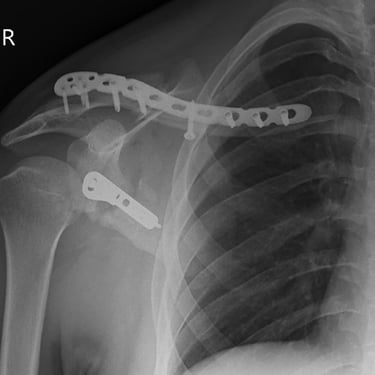

Gallery